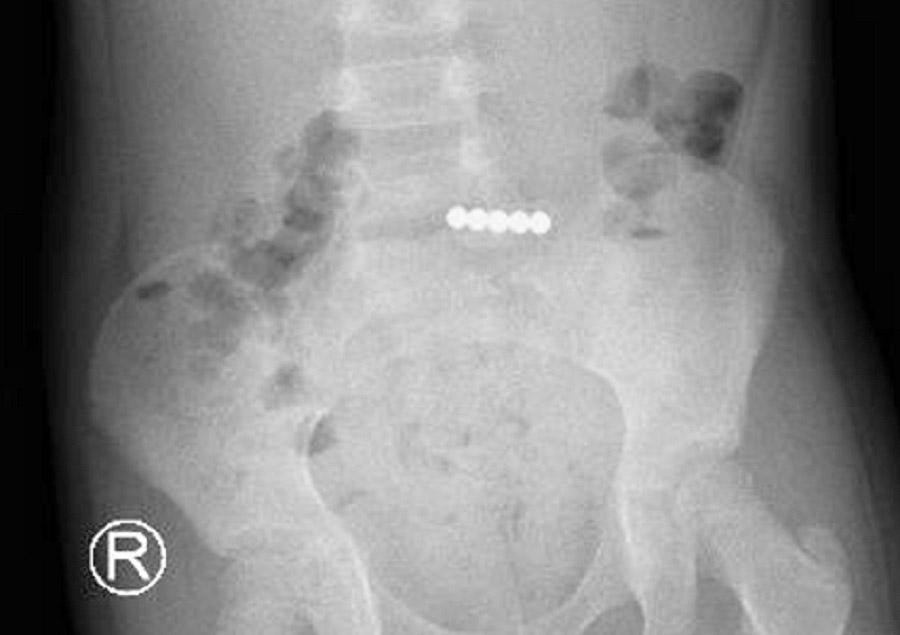

| Khi đang ngậm trong miệng, bệnh nhi đã sơ ý nuốt cả 5 viên bi vào đường tiêu hóa |

Thời điểm nhập viện trẻ có biểu hiện đau bụng, nôn ói, tâm lý hoảng loạn. Kết quả chụp X-quang bụng phát hiện dị vật đã xếp hàng dính chặt vào nhau ở ruột non của bệnh nhi. Sau hội chẩn nhanh, các bác sĩ đã quyết định thực hiện phương pháp nội soi đường tiêu hóa lấy dị vật. Bằng những thủ thuật chuyên môn, ê kíp nội soi đã đưa dị vật từ ruột non lên dạ dày và gắp ra 5 viên bi nam châm dính vào nhau.